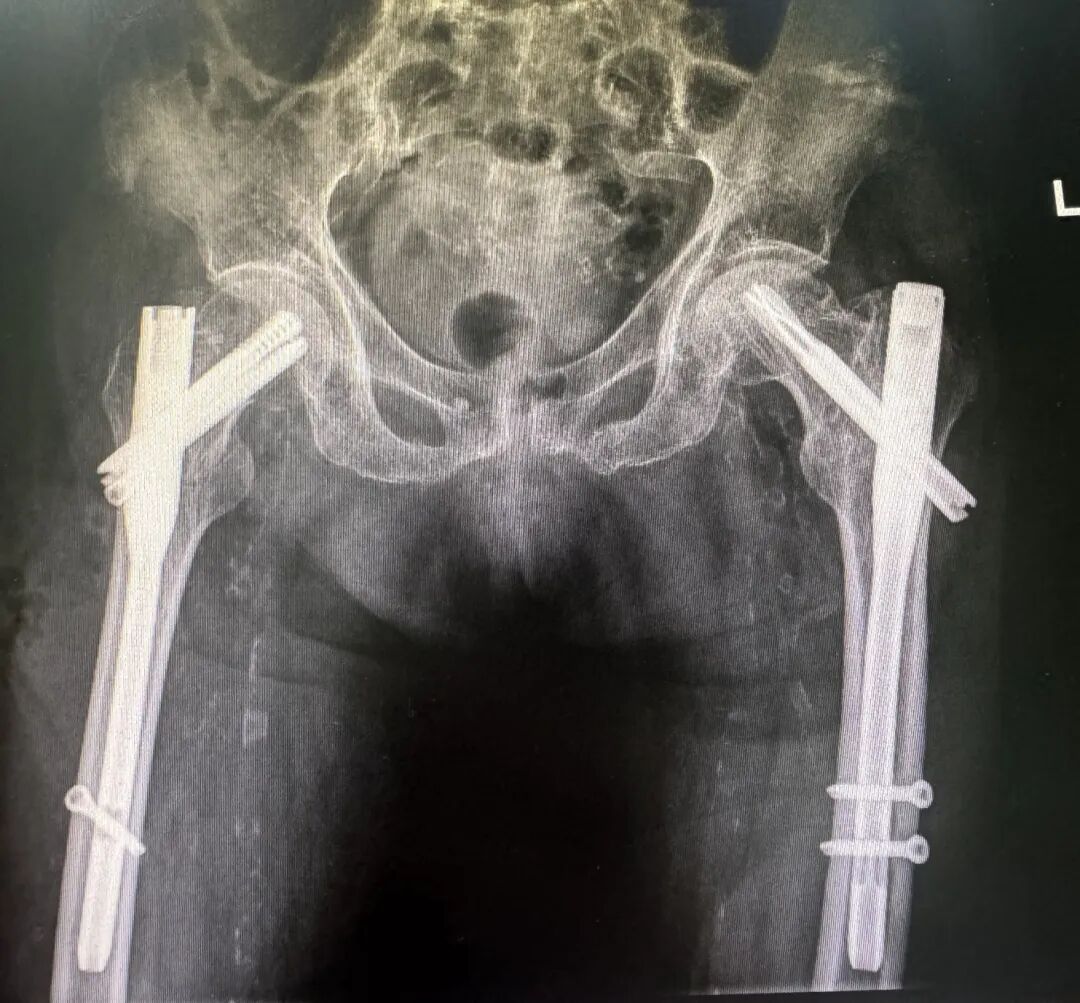

术后影像

经过详尽准备后,余新平副院长和团队成员为老人进行了手术,在骨科、麻醉科、手术室等多学科的紧密配合和通力协作下,顺利攻克了各个难点。术后张奶奶各项指标良好。在我院ICU的监护下,张奶奶的疼痛显著减轻,晚上终于能睡着了。

一周后,张奶奶顺利出院。